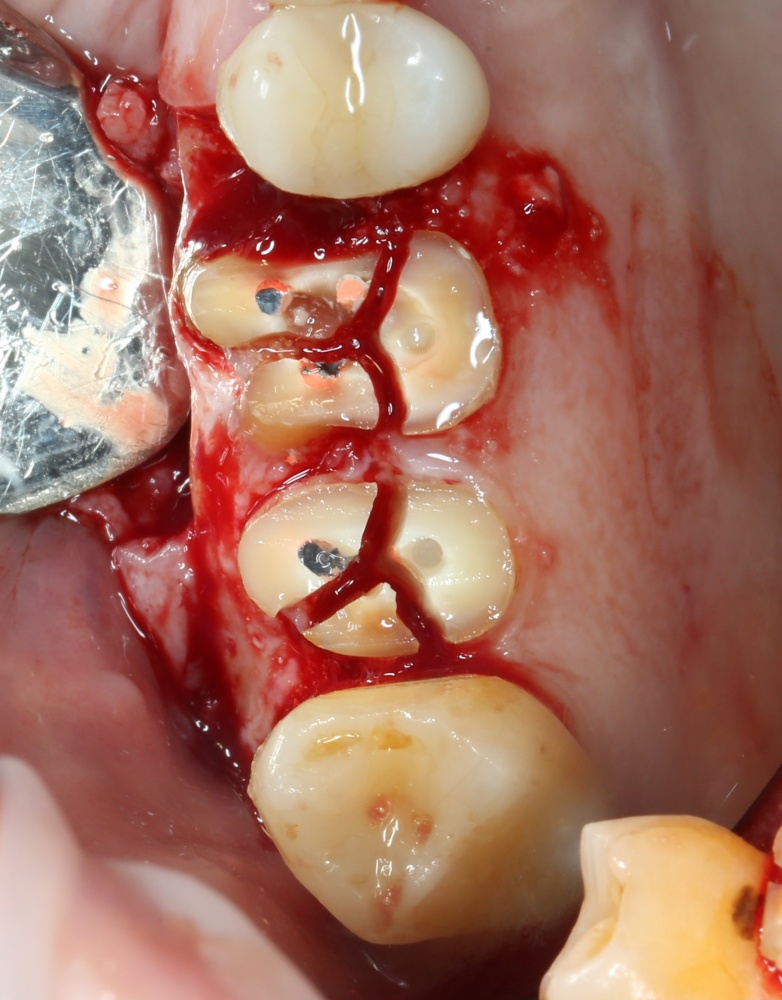

Кстати, обрати внимание на ширину альвеолярного гребня (левая картинка). Она чуть меньше 3 мм. Это объясняет, почему я засомневался в возможности установки имплантатов одновременно с остеопластикой. Понятно и без КЛКТ.

Наперво, мне нужно удалить разрушенный зуб и получить костный аутотрансплантат.

Возвращаемся к основной операционной области. Еще раз посмотрим на альвеолярный гребень, поофигеваем от его ширины и моих грандиозных планов: